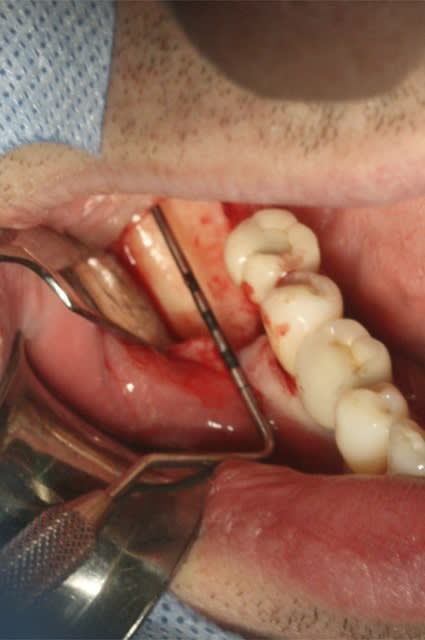

image1: incision verticale + décollement du lambeau de proche en proche

Désolé pour la qualité, c'est tout ce que j'ai..